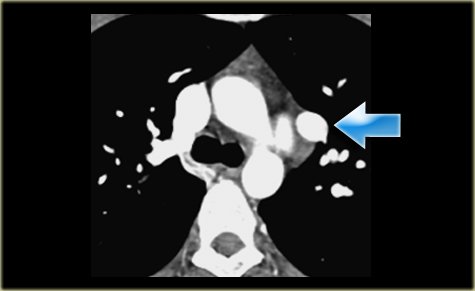

Describe the images on the left and then continue reading.

On the left side there is a vascular structure, that runs inferiorly below the level of the left hilum and enters into a dilated coronary sinus.

The diagnosis is left or double superior vena cava.

Left Superior Intercostal Vein.

This is an anastomosis between the accessory hemiazygos vein and the left brachiocephalic vein.

It courses along the lateral margin of the aortic arch (‘aortic nipple’).

It is a normal variant and if you look for this structure you will frequently notice it.

On the left a patient with a left superior intercostal vein.

Notice the ‘aortic nipple sign’.

On the left another example of a left superior intercostal vein.

It courses along the lateral margin of the aortic arch from the the accessory hemiazygos vein to the left brachiocephalic vein.